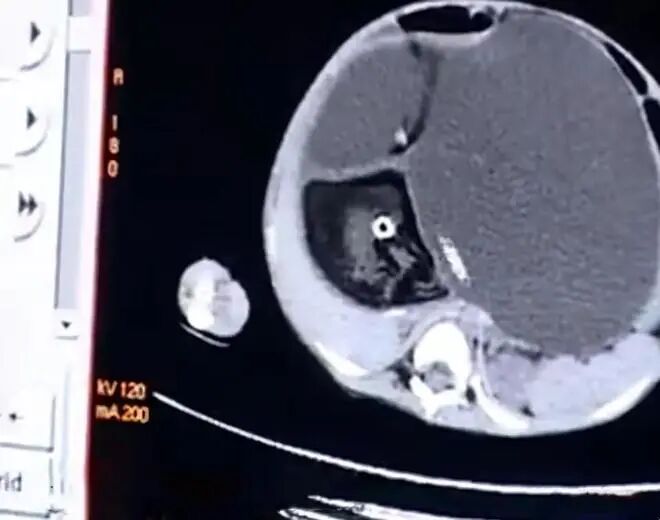

医生在梦茹的体内,发现了不完整的死胎,影像中还能清楚看到毛发和牙齿。

只不过这种“怀孕”,有一个专业的医学名词:先天性畸胎瘤。

医生推测,很可能是梦茹在母亲体内时,同时发育了异常胚胎,进入到小梦茹的体内。

医生表示,畸胎瘤并不罕见,但是这么大的瘤子却十分罕见,更别说是长在婴儿体内了。

当时小梦茹的体重只有10公斤,瘤子却有4、5公斤重,占了体重的一半。

肿瘤已经严重压迫内脏,一旦打开腹腔,肺压急剧减小,有可能引发肺水肿,造成呼吸衰竭。

稍微搬动肿瘤,还有可能造成梦茹的心跳停止。